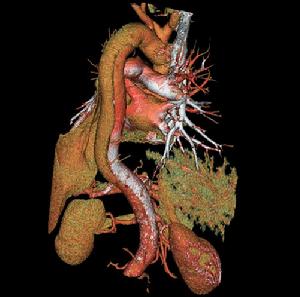

主動脈夾層(aortic dissection)指主動脈腔內的血液通過內膜的破口進入主動脈壁中層而形成的血腫,並非主動脈壁的擴張,有別於主動脈瘤,過去此種情況被稱為主動脈夾層動脈瘤(aortic dissecting aneurysm),現多改稱為主動脈夾層血腫(aortic dissectin ghematoma),或主動脈夾層分離,簡稱主動脈夾層。動脈夾層是指由於內膜局部撕裂,受到強有力的血液衝擊,內膜逐步剝離、擴展,在動脈內形成真、假兩腔。從而導致一些列包括撕裂樣疼痛的表現。主動脈是身體的主幹血管,承受直接來自心臟跳動的壓力,血流量巨大,出現內膜層撕裂,如果不進行恰當和及時的治療,破裂的機會非常大,死亡率也非常高。

主動脈夾層此外,Daily和Miller又將主動脈夾層分為兩型:凡升主動脈受累者為A型(包括DeBakeyⅠ型和Ⅱ型),病變在左鎖骨下動脈遠端開口為B型(即DeBakeyⅢ型),A型約占全部病例的2/3,B型約占1/3。

主動脈夾層動脈瘤(二)X線 胸部平片見上縱隔或主動脈弓影增大,主動脈外形不規則,有局部隆起。如見主動脈內膜鈣化影,可準確測量主動脈壁的厚度。正常在2~3mm,增到10mm時則提示夾層分離可能性,若超過10mm則可肯定為本病。主動脈造影可以顯示裂口的部位,明確分支和主動脈瓣受累情況,估測主動脈瓣關閉不全的嚴重程度。缺點是它屬於有創性檢查,術中有一定危險性。CT可顯示病變的主動脈擴張。發現主動脈內膜鈣化優於X線平片,如果鈣化內膜向中央移位則提示主動脈夾層,如向外圍移位提示單純主動脈瘤。此外CT還可顯示由於主動脈內膜撕裂所致內膜瓣,此瓣將主動脈夾層分為真腔和假腔。CT對降主動脈夾層分離準確性高,主動脈升、弓段由於動脈扭曲,可產生假陽性或假陰性。但CT對確定裂口部位及主動脈分支血管的情況有困難,且不能估測主動脈瓣關閉不全的存在。

(四)磁共振成像(MRI) MRI能直接顯示主動脈夾層的真假腔,清楚顯示內膜撕裂的位置和剝離的內膜片或血栓。能確定夾層的範圍和分型,以及與主動脈分支的關係。但其不足是費用高,不能直接檢測主動脈瓣關閉不全,不能用於裝有起搏器和帶有人工關節、鋼針等金屬物的病人。